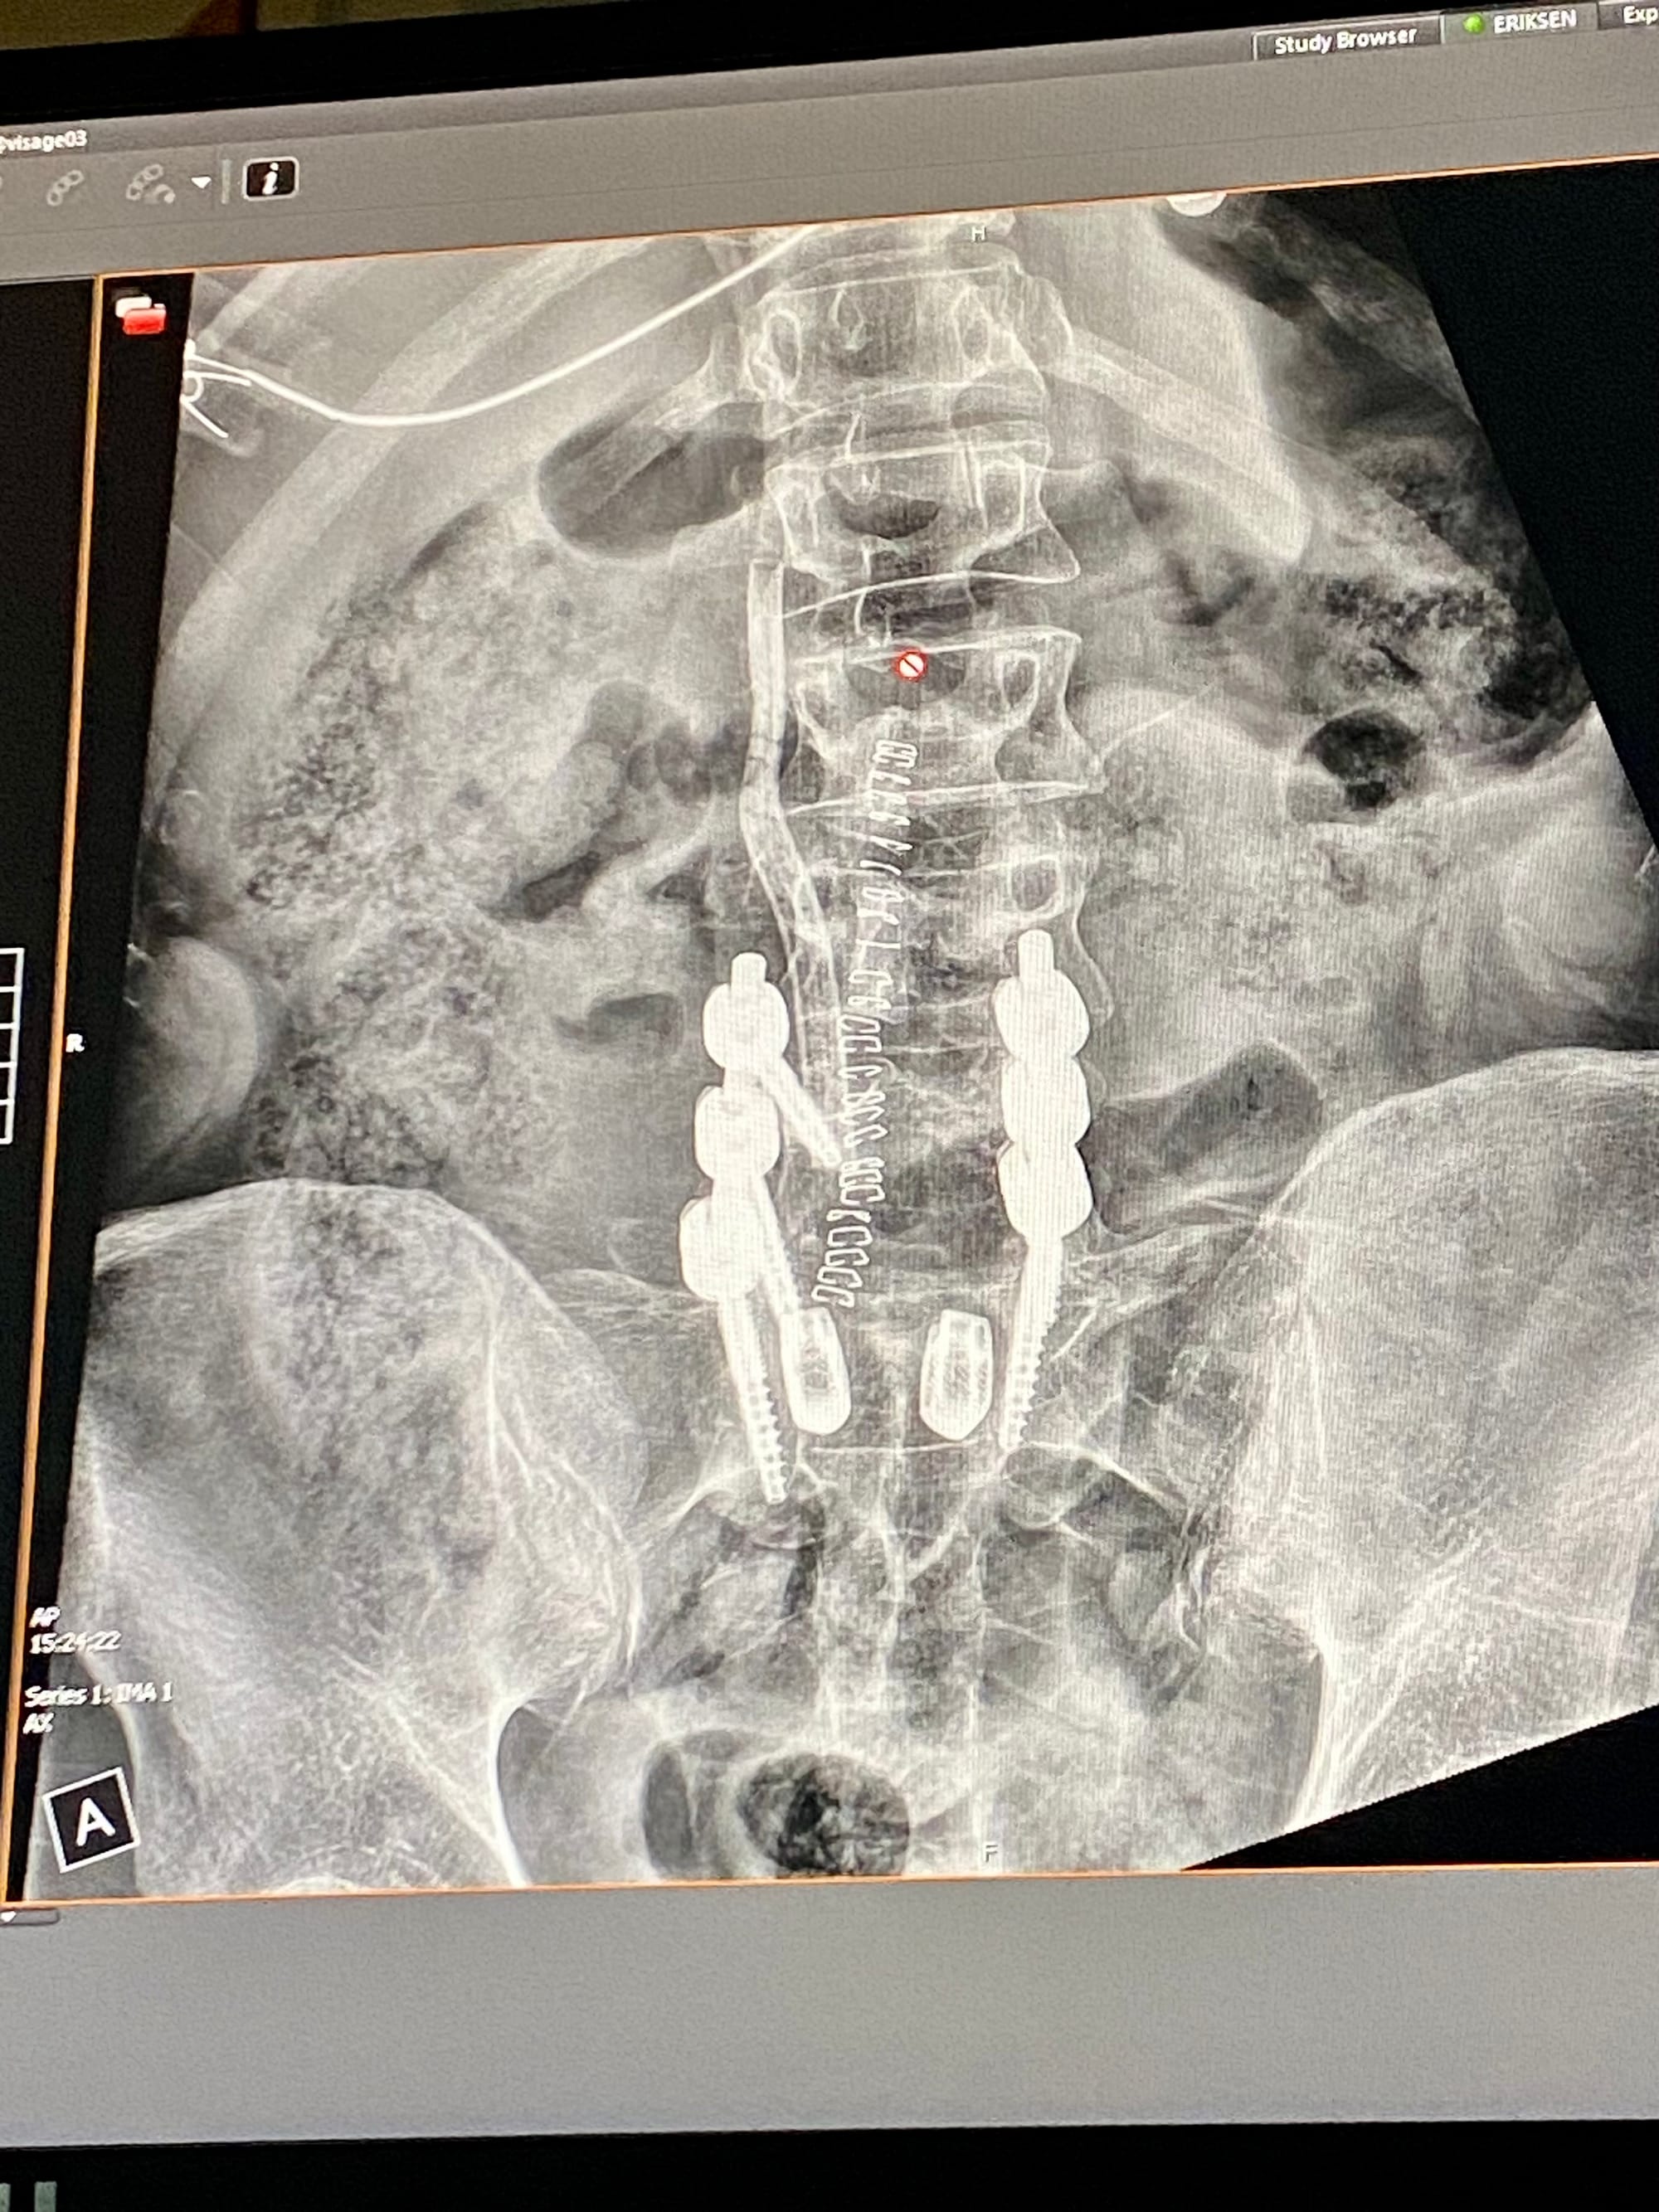

I underwent lumbar fusion surgery because my life-long chronic back pain reached a level that I could no longer gig. I could no longer think clearly and move easefully.

The fusion itself appears to have been a success, but an unexpected inflammation around my low-back nerve roots has made it impossible for me to sit, stand, or walk without debilitating pain and numbness in my left leg. I have been mostly confined to a bed since October 29th. I make myself get up with a walker to keep myself moving and take care of some basic necessities, but the effort leaves me panting and writhing in pain.